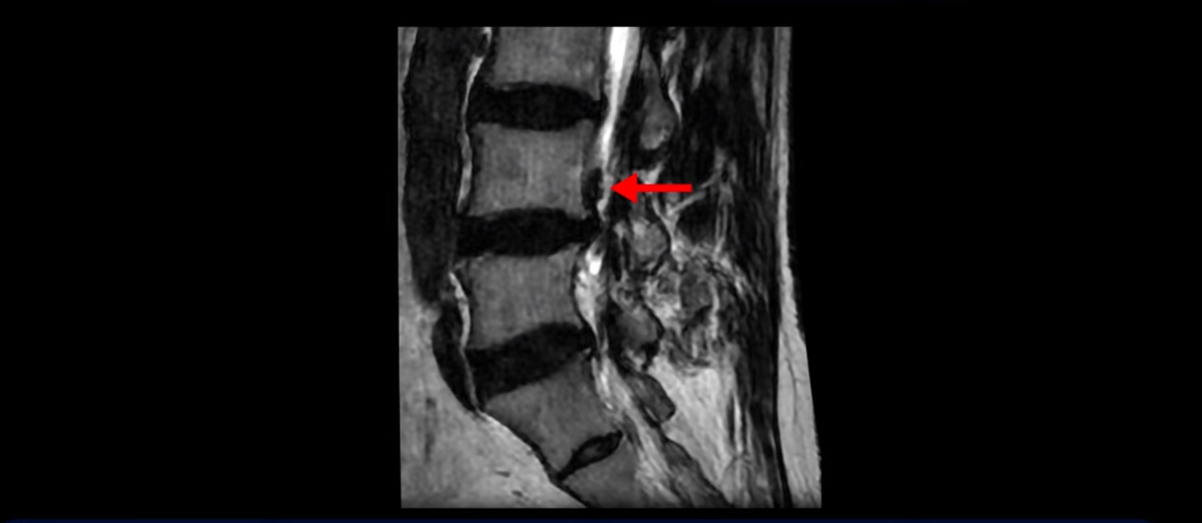

하지만 이분의 갑작스러운 통증을 일으키는 원인은 4번 5번에 발생한 디스크 파열입니다.

이분은 왼쪽 무릎 아래로 본인 표현으로는 다리를 잘라 버리고 싶다고 할 정도의 심한 통증이 있는데 보통 이런 표현은 디스크 파열이 발생했을 때 많이 사용하는 표현입니다. 이분 4번 5번 디스크를 자세히 보면 왼쪽으로 파열되어 밀려 올라간 디스크 수핵을 볼 수 있습니다.

옆에서도 보이지만 단면에서도 왼쪽으로 심하게 밀려나온 수핵이 잘 보입니다.